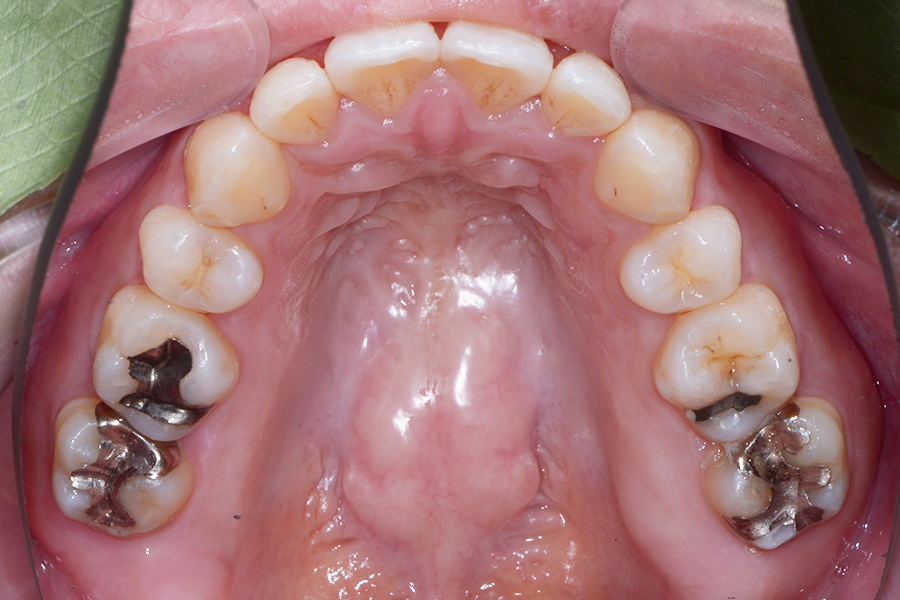

【30代女性】

引っ込んでいる部分を治したい

【矯正歯科治療】

- 担当医

- 三留先生

- 主訴

- 引っ込んでいる部分を治したい

- 期間

- 7か月

- 費用

- 治療費30万+30万(別途調整料)

- 治療内容

- 上下顎リンガル矯正(裏側矯正)

- 治療に伴うリスク

- 後戻り